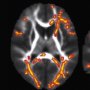

The dorsolateral prefrontal cortex, depicted in blue and red, is larger and linked with better function in those who carry one copy of the KLOTHO gene variant. Illustration by Michael Griffin Kelly

They found that the KLOTHO gene variant predicted the size of a region called the right dorsolateral prefrontal cortex (rDLPFC), which is especially vulnerable to atrophy as people age. Deterioration in this area may be one reason why older people have difficulty suppressing distracting information and doing more than one thing at a time.